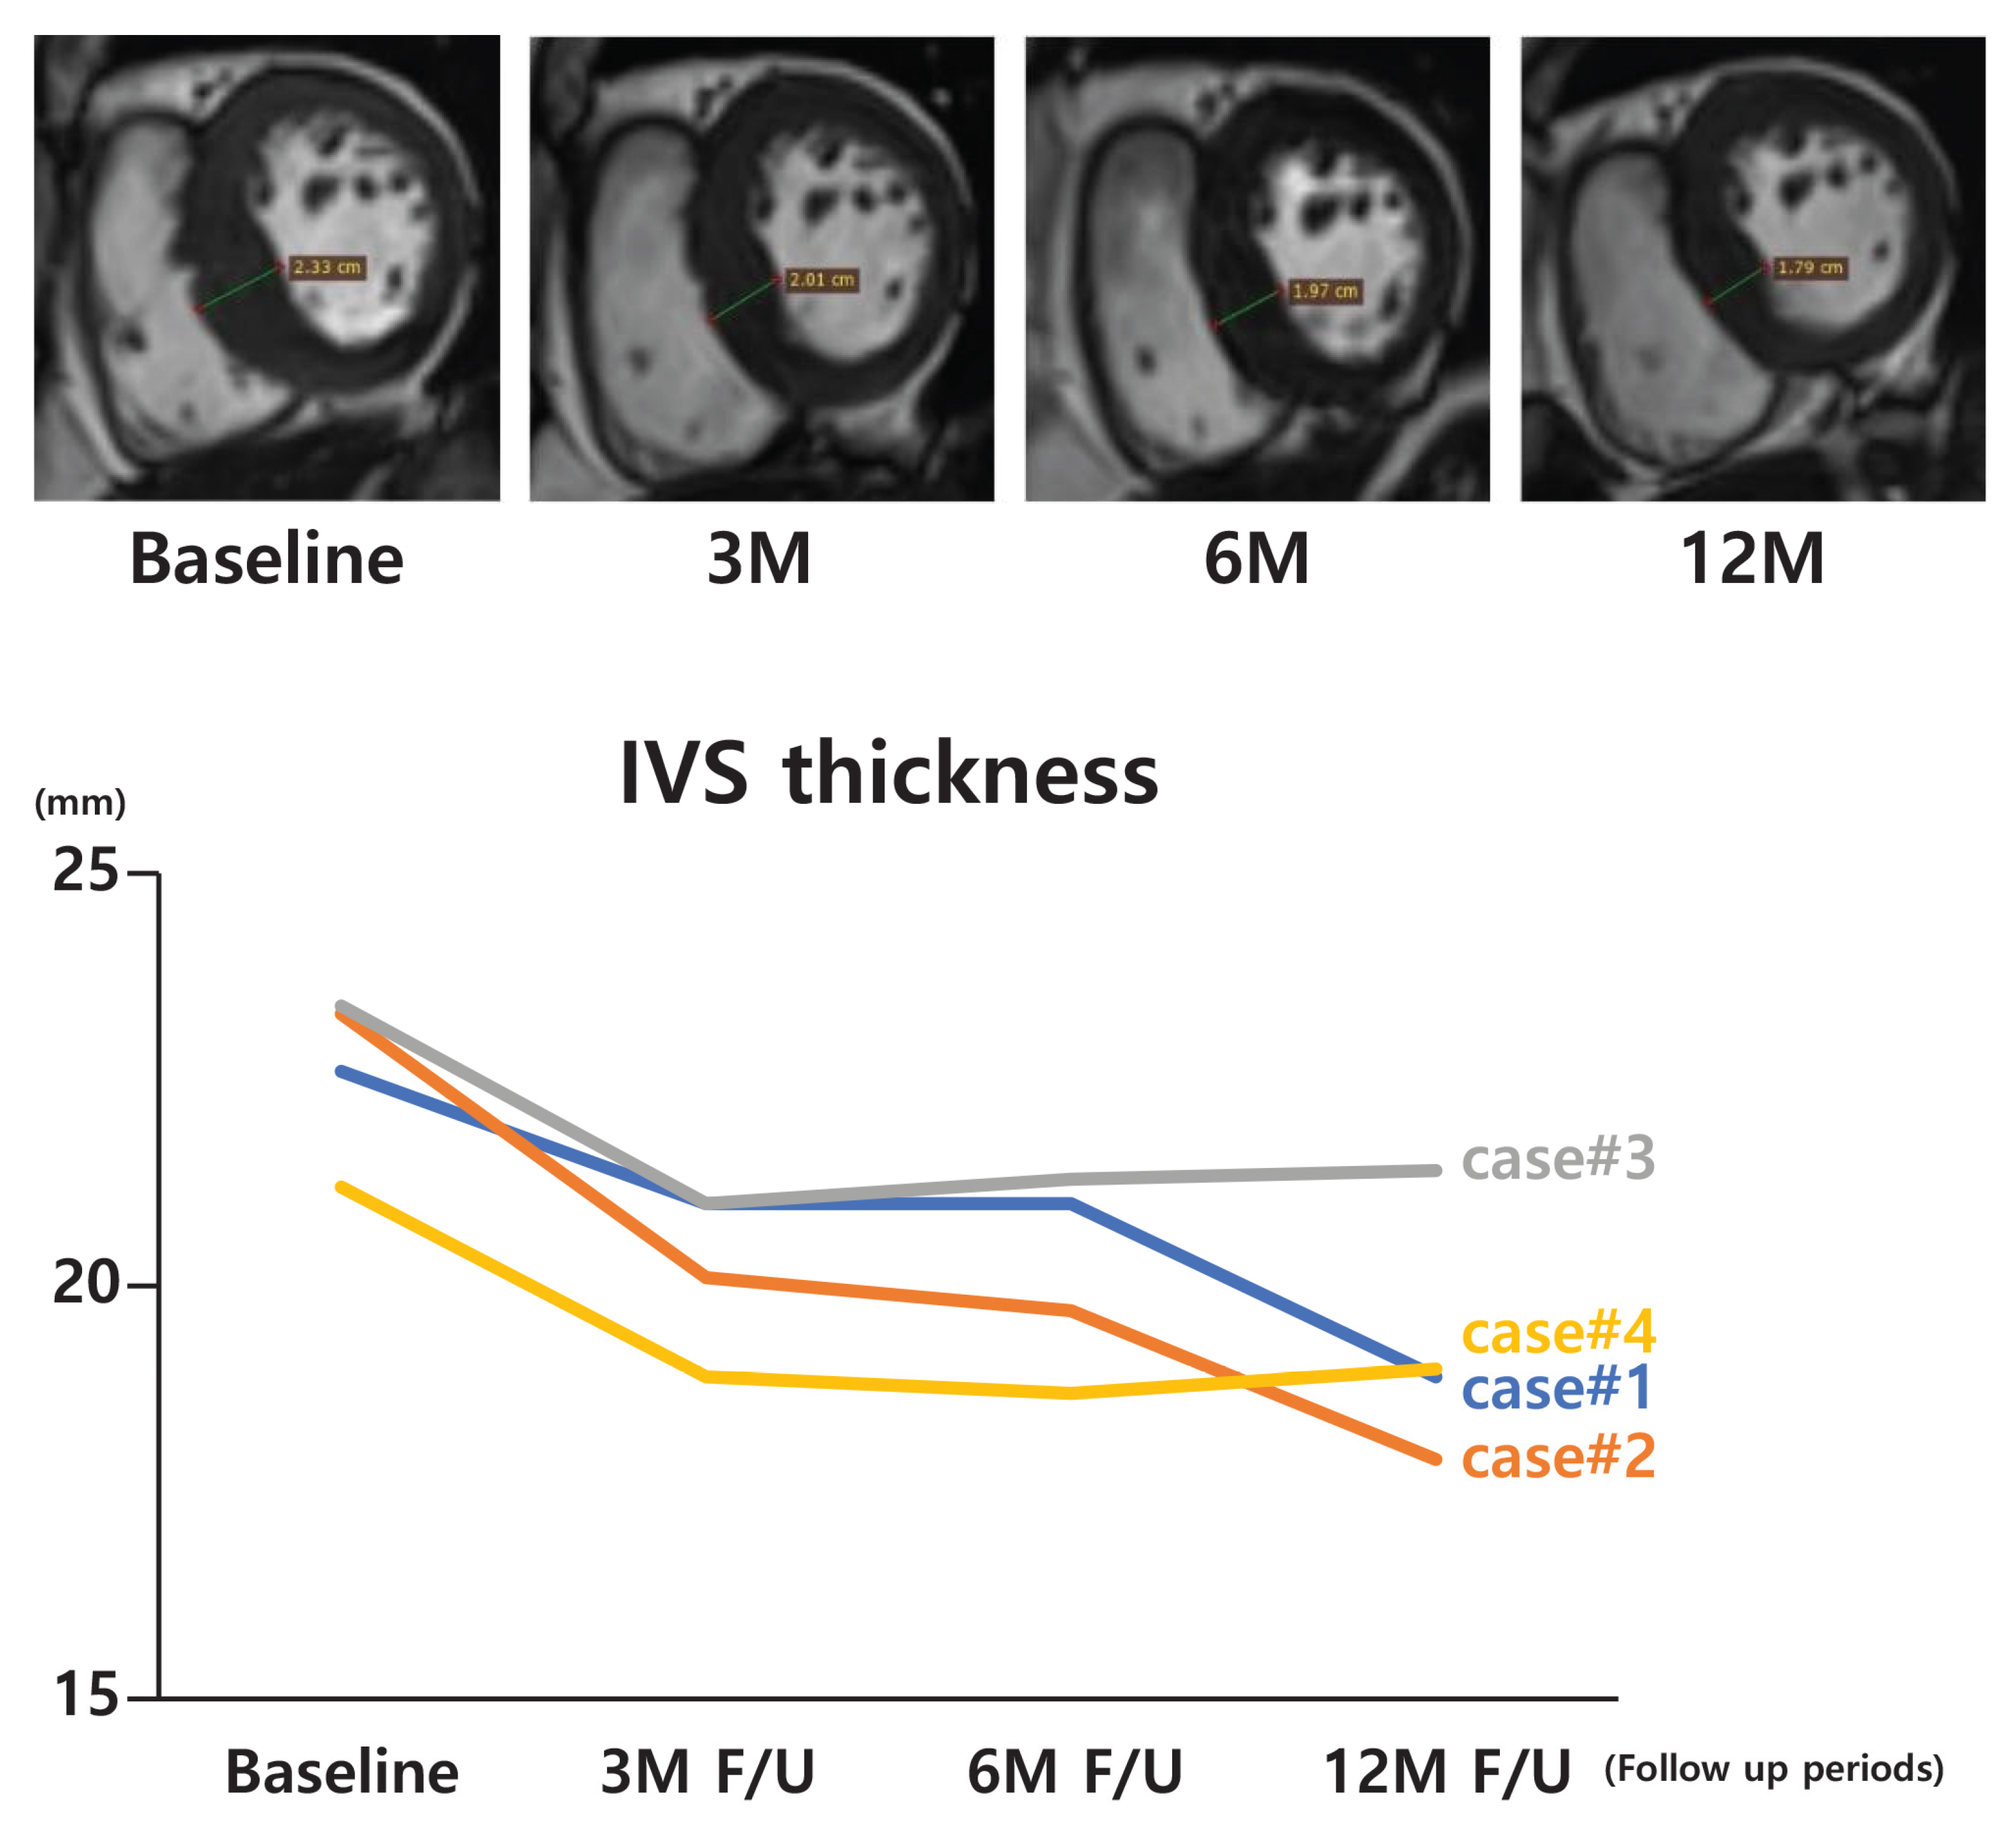

| Case | Computed Tomography or MRI Measurement Data (Interventricular Septal Thickness) | |||

|---|---|---|---|---|

| Baseline | 3 M | 6 M | 12 M | |

| 1 * | 22.6 | 21.0 | - | 18.9 |

| 2 | 23.3 | 20.1 | 19.7 | 17.9 |

| 3 | 23.4 | 21.0 | 21.3 | 21.4 |

| 4 | 21.2 | 18.9 | 18.7 | 19.0 |